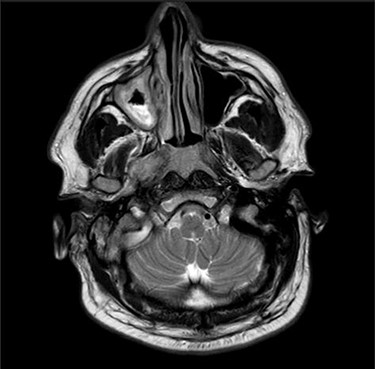

Computerized tomography (CT) of the internal meatuses demonstrated soft tissue thickening of the right middle ear cavity, aditus, antrum and mastoid air cells in keeping with otomastoiditis (Fig. 1), but no destructive or erosive pathology to account for the multiple neuropathies elicited on examination. A subsequent magnetic resonance imaging (MRI) scan demonstrated a 2.5 centimeter (cm) right skull base inflammatory mass, involving the internal carotid artery and jugular foramen (Fig. 2). Anti-microbial therapy was subsequently changed to intravenous meropenem and topical ciprofloxacin ear drops. The patient underwent a right cortical mastoidectomy and grommet insertion at Day 5, with well-pneumatized air cells and inflammatory tissue observed within the aditus.

Axial CT image slice showing opacification of the right middle ear cavity and mastoid air cells.